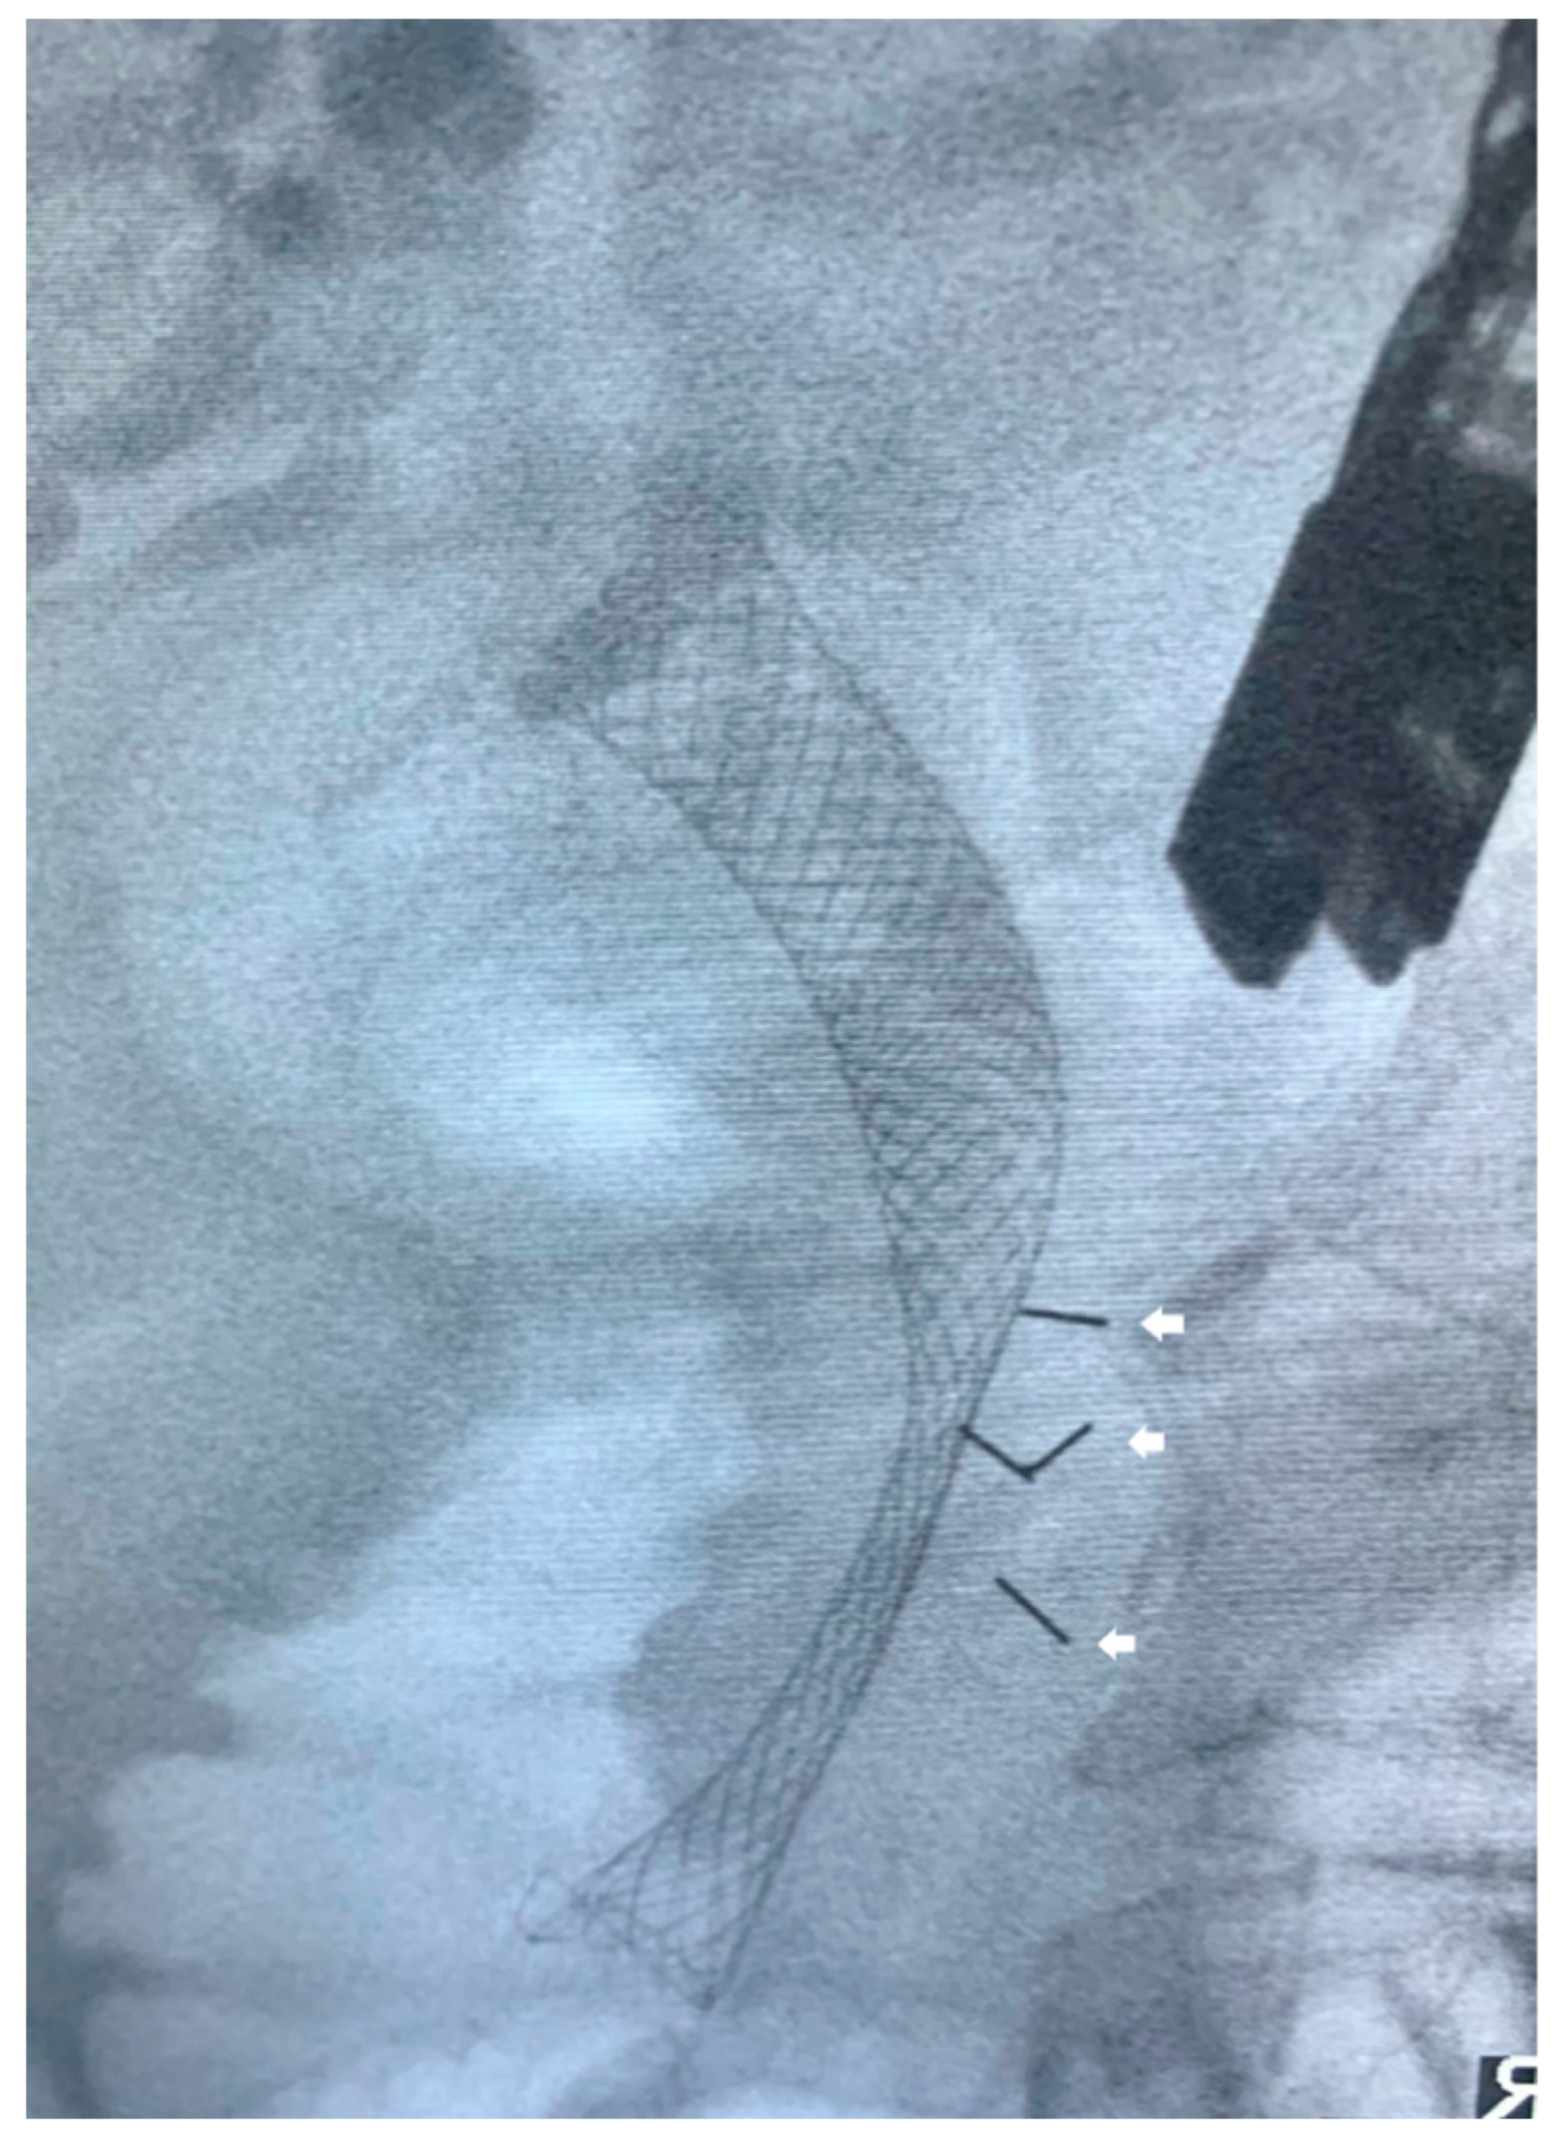

- Park, W.G.; Yan, B.M.; Schellenberg, D.; Kim, J.; Chang, D.T.; Koong, A.; Patalano, C.; Van Dam, J. EUS-guided gold fiducial insertion for image-guided radiation therapy of pancreatic cancer: 50 successful cases without fluoroscopy. Gastrointest. Endosc. 2010, 71, 513–518. [Google Scholar] [CrossRef]

- Sanders, M.K.; Moser, A.J.; Khalid, A.; Fasanella, K.E.; Zeh, H.J.; Burton, S.; McGrath, K. EUS-guided fiducial placement for stereotactic body radiotherapy in locally advanced and recurrent pancreatic cancer. Gastrointest. Endosc. 2010, 71, 1178–1184. [Google Scholar] [CrossRef]

- Varadarajulu, S.; Trevino, J.M.; Shen, S.; Jacob, R. The use of endoscopic ultrasound-guided gold markers in image-guided radiation therapy of pancreatic cancers: A case series. Endoscopy 2010, 42, 423–425. [Google Scholar] [CrossRef]

- Choi, J.-H.; Seo, D.-W.; Park, D.H.; Lee, S.K.; Kim, M.-H. Fiducial Placement for Stereotactic Body Radiation Therapy under Only Endoscopic Ultrasonography Guidance in Pancreatic and Hepatic Malignancy: Practical Feasibility and Safety. Gut Liver 2014, 8, 88–93. [Google Scholar] [CrossRef] [PubMed]

- Dávila Fajardo, R.; Lekkerkerker, S.J.; van der Horst, A.; Lens, E.; Bergman, J.J.; Fockens, P.; Bel, A.; van Hooft, J.E. EUS-guided fiducial markers placement with a 22-gauge needle for image-guided radiation therapy in pancreatic cancer. Gastrointest Endosc. 2014, 79, 851–855. [Google Scholar] [CrossRef] [PubMed]

- Dhadham, G.C.; Hoffe, S.; Harris, C.L.; Klapman, J.B. Endoscopic ultrasound-guided fiducial marker placement for im-age-guided radiation therapy without fluoroscopy: Safety and technical feasibility. Endosc. Int. Open 2016, 4, E378–E382. [Google Scholar] [PubMed]

- Tabernero, S.; Prados, S.; Rubio, M.D.C.; de la Morena, F.; López, M.; Sánchez, E. Endoscopic ultrasound-guided fiducial placement in pancreatic tumors: Safety and technical feasibility. Rev. Esp. Enferm. Dig. 2019, 111, 425–430. [Google Scholar] [CrossRef]

- Khashab, M.A.; Kim, K.J.; Tryggestad, E.J.; Wild, A.T.; Roland, T.; Singh, V.K.; Lennon, A.M.; Shin, E.J.; Ziegler, M.A.; Sharaiha, R.Z.; et al. Comparative analysis of traditional and coiled fiducials implanted during EUS for pancreatic cancer patients receiving stere-otactic body radiation therapy. Gastrointest. Endosc. 2012, 76, 962–971. [Google Scholar] [CrossRef]